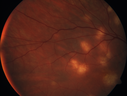

31 year old man with vision loss in the right eye more than the left eye. He has an anaplastic astrocytoma diagnosed 10/2017 the first one was 10/2014. These are different locations. They are treating them with Chemotherapy and Avastin. It might be that one might have spread from the other. He was clean for 3 years. He is on Avastin and Temozolomide but his blood counts have been good. December 2017 he had a herpes superficial infection in the right eye which responded to treatment. The last neurosurgery was October 2017. Going to Duke June 5 and seeing a neuroophthalmologist there. VA OD: Dcc20/40 PH20/25 NccJ5 VA OS: Dcc20/16 PH20/10 NccJ1+ His fundus is presumably nocardia, pneumocystis, aspergillis or cryptococcus. His LP was negative and he was tried on a course of antifungals. He was then lost to followup

Multifocal Choroiditis - Pneumocystis - aspergillis - cryptococcus730 views31 year old male with anaplastic astrocytoma on chemotherapy with mild vision loss in the right eye. LP did not reveal organism. He was placed on a trial of anti-fungal medications and lost to follow-up00000